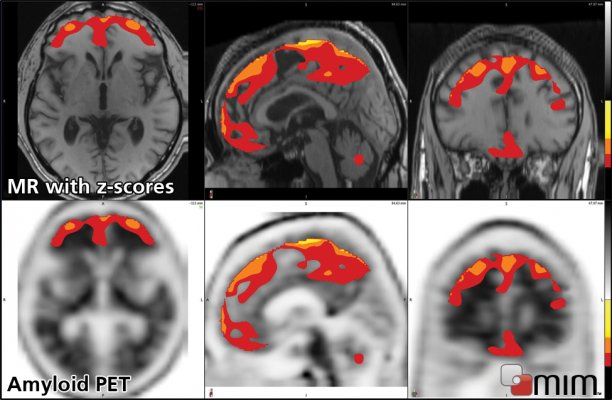

June 11, 2012 — MIM Software is currently preparing MIMneuro version 5.5.0 for release in June. MIMneuro is vendor-neutral software indicated for quantitative and statistical analysis to aid in the interpretation of PET (positron emission tomography) and SPECT (single photon emission computed tomography) brain images. The new version will include two enhancements to make it well suited for quantitative analysis of amyloid PET images.

The BrainAlign deformable registration algorithm now includes the ability to deformably register to multiple templates simultaneously. With this landmark-based deformable registration approach, local differences in anatomy are resolved more accurately than with affine registration. The variability in uptake patterns with targeted tracers such as amyloid confounds single template registration approaches. By simultaneously using multiple templates, the BrainAlign algorithm registers these images.

Additionally, MIM Software has worked with experts to define and release its third anatomical brain atlas. This probabilistic amyloid atlas is a tool specifically tuned for performing quantitative regional analysis on amyloid PET images.

MIMneuro combines these new features with existing tools – including voxel-based analysis, region-based analysis, SUVR computation, cluster analysis and surface projection analysis – into comprehensive quantitative functional neuroimaging software.